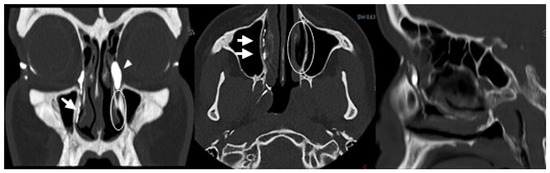

Background: Conventional CT–dacryocystography (CT-DCG) requires canalicular cannulation and forced contrast injection, which may distort anatomy and cause discomfort. This study describes a non-cannulated CT-DCG protocol using dropwise iodixano...